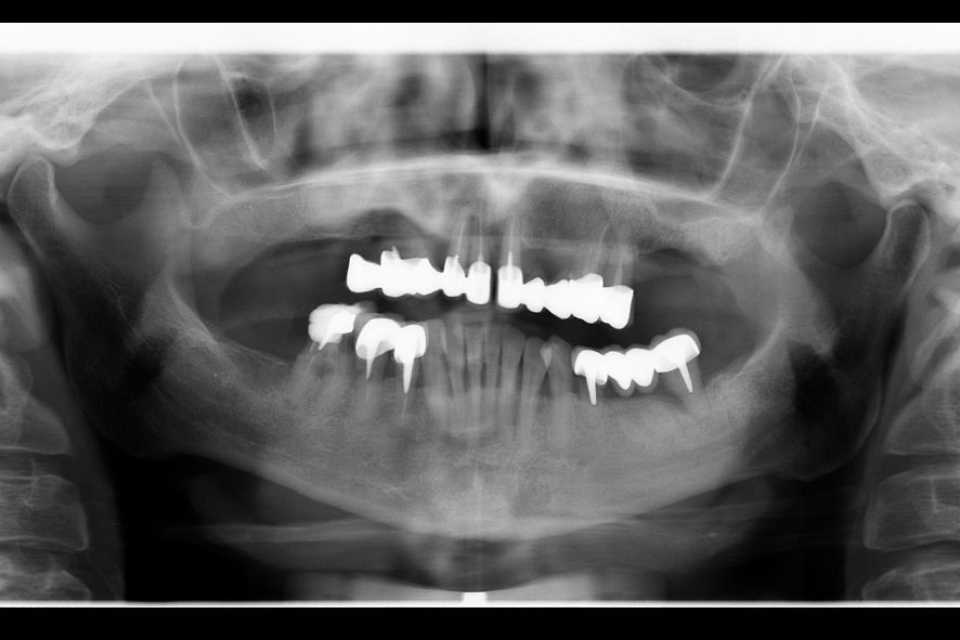

În urma examenului de specialitate, s-a constatat prezența unei punți totale la nivelul maxilarului și a două lucrări vechi la nivelul mandibulei, în zonele laterale premolar-molar. Dintii stâlpi prezentau multiple pungi parodontale, leziuni apicale și mobilitate accentuată.

Împreună cu pacienta, am optat pentru un tratament complex, realizat într-o singură ședință. S-au efectuat extracțiile dinților parodontotici, chiuretajul pungilor parodontale și inserarea a 4 implanturi Mega-Gen AnyRidge la nivelul maxilarului. Cu ajutorul capelor multiunit, s-a reușit protezarea imediată, prin aplicarea unei lucrări provizorii din acrilat, la doar 24 de ore de la intervenție. După 2 luni, tratamentul a fost finalizat prin realizarea unei lucrări definitive, înșurubabile, din ceramică pe suport de zirconiu, cu 12 elemente.

La nivelul mandibulei, reabilitarea zonelor laterale premolar-molar s-a realizat prin inserarea a câte două implanturi pe fiecare parte, protezate după 2 luni cu două lucrări din ceramică pe suport de zirconiu, cimentate. Dintii restanți ai mandibulei au fost conservați după tratamentul parodontal și solidarizați printr-o contenție linguală.